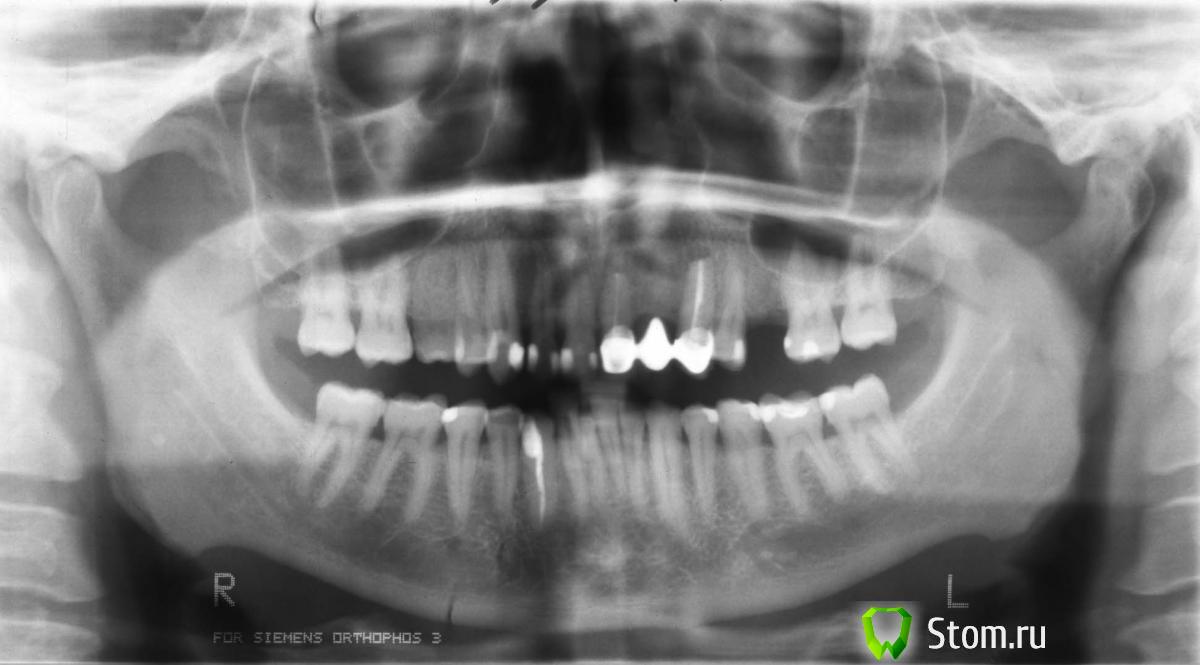

Здравствуйте. Я в первый раз собираюсь ставить импланты. У меня проблемы с передними верхними зубами. Начались они около 15 лет назад. Сначала выросла киста на левой верхней двойке. Сделали резекцию, но через несколько лет она снова выросла и перекинулась на соседние единицу и тройку. Пришлось удалить двойку и сделать резекцию единицы и тройки. Тогда же поставили мост, который стоит и сейчас(на фото). Но сейчас, со слов врача, опять выросла киста, уже в третий раз. Врач предлагает два варианта:

1)Удалить единицу и сделать еще одну резекцию тройки, после чего поставить импланты на единицу и двойку.

2)Удалить единицу и тройку, на их место поставить два импланта и на них закрепить мост из трех зубов. Причем этот вариант врач считает предпочтительным, т.к. по его мнению тройку рано или поздно все равно придется удалять.

1)Я прикрепил файлы со снимками. Скажите, у меня действительно кисты и на единице и на тройке? И насколько там все плохо?

3)Двойка у меня была удалена четыре года назад, кость в этом месте стала тоньше. Может ли это быть причиной не позволяющей ставить туда имплант?